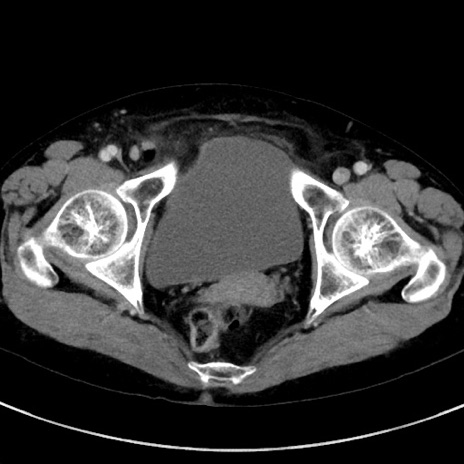

症例23(横断像)

【症例】70歳代女性

【主訴】下腹部痛・嘔吐

【現病歴】2日前より腹痛あり。昨日嘔吐あり。症状改善しないため来院。

【既往歴】胃GISTに対して胃部分切除後。

【身体所見】BT 37.1℃、BP 128/77mmHg、腹部:平坦・軟、下腹部に圧痛あり。

【データ】WBC 10200、CRP 0.31